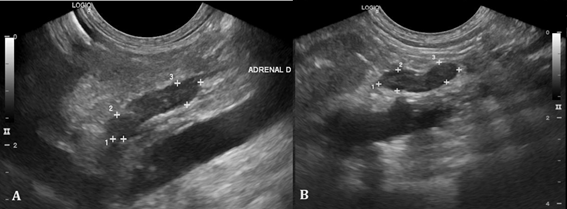

Abdominal ultrasound revealed a decrease in the size of adrenal glands (Figure 2) and hepatosplenomegaly compatible with hepatic steatosis (Figure 3).

Figure 2 Ultrasound of adrenal glands. A. Right adrenal gland measuring 1.44 x 0.46 x 0.43cm (length x height of cranial pole x height of caudal pole). B. Left adrenal gland measuring 1.12 x 0.36 x 0.33cm (length x height of cranial pole x height of caudal pole).

Another finding after chronic exogenous administration of corticosteroids is the progressive atrophy of the adrenal gland12 caused by the suppression of CRH (Corticotropin Releasing Hormone) produced by the hypothalamus, with a consequent decrease in the plasma concentration of ACTH (Adrenocorcotrophic Hormone),2,4 according to seen on abdominal ultrasound.